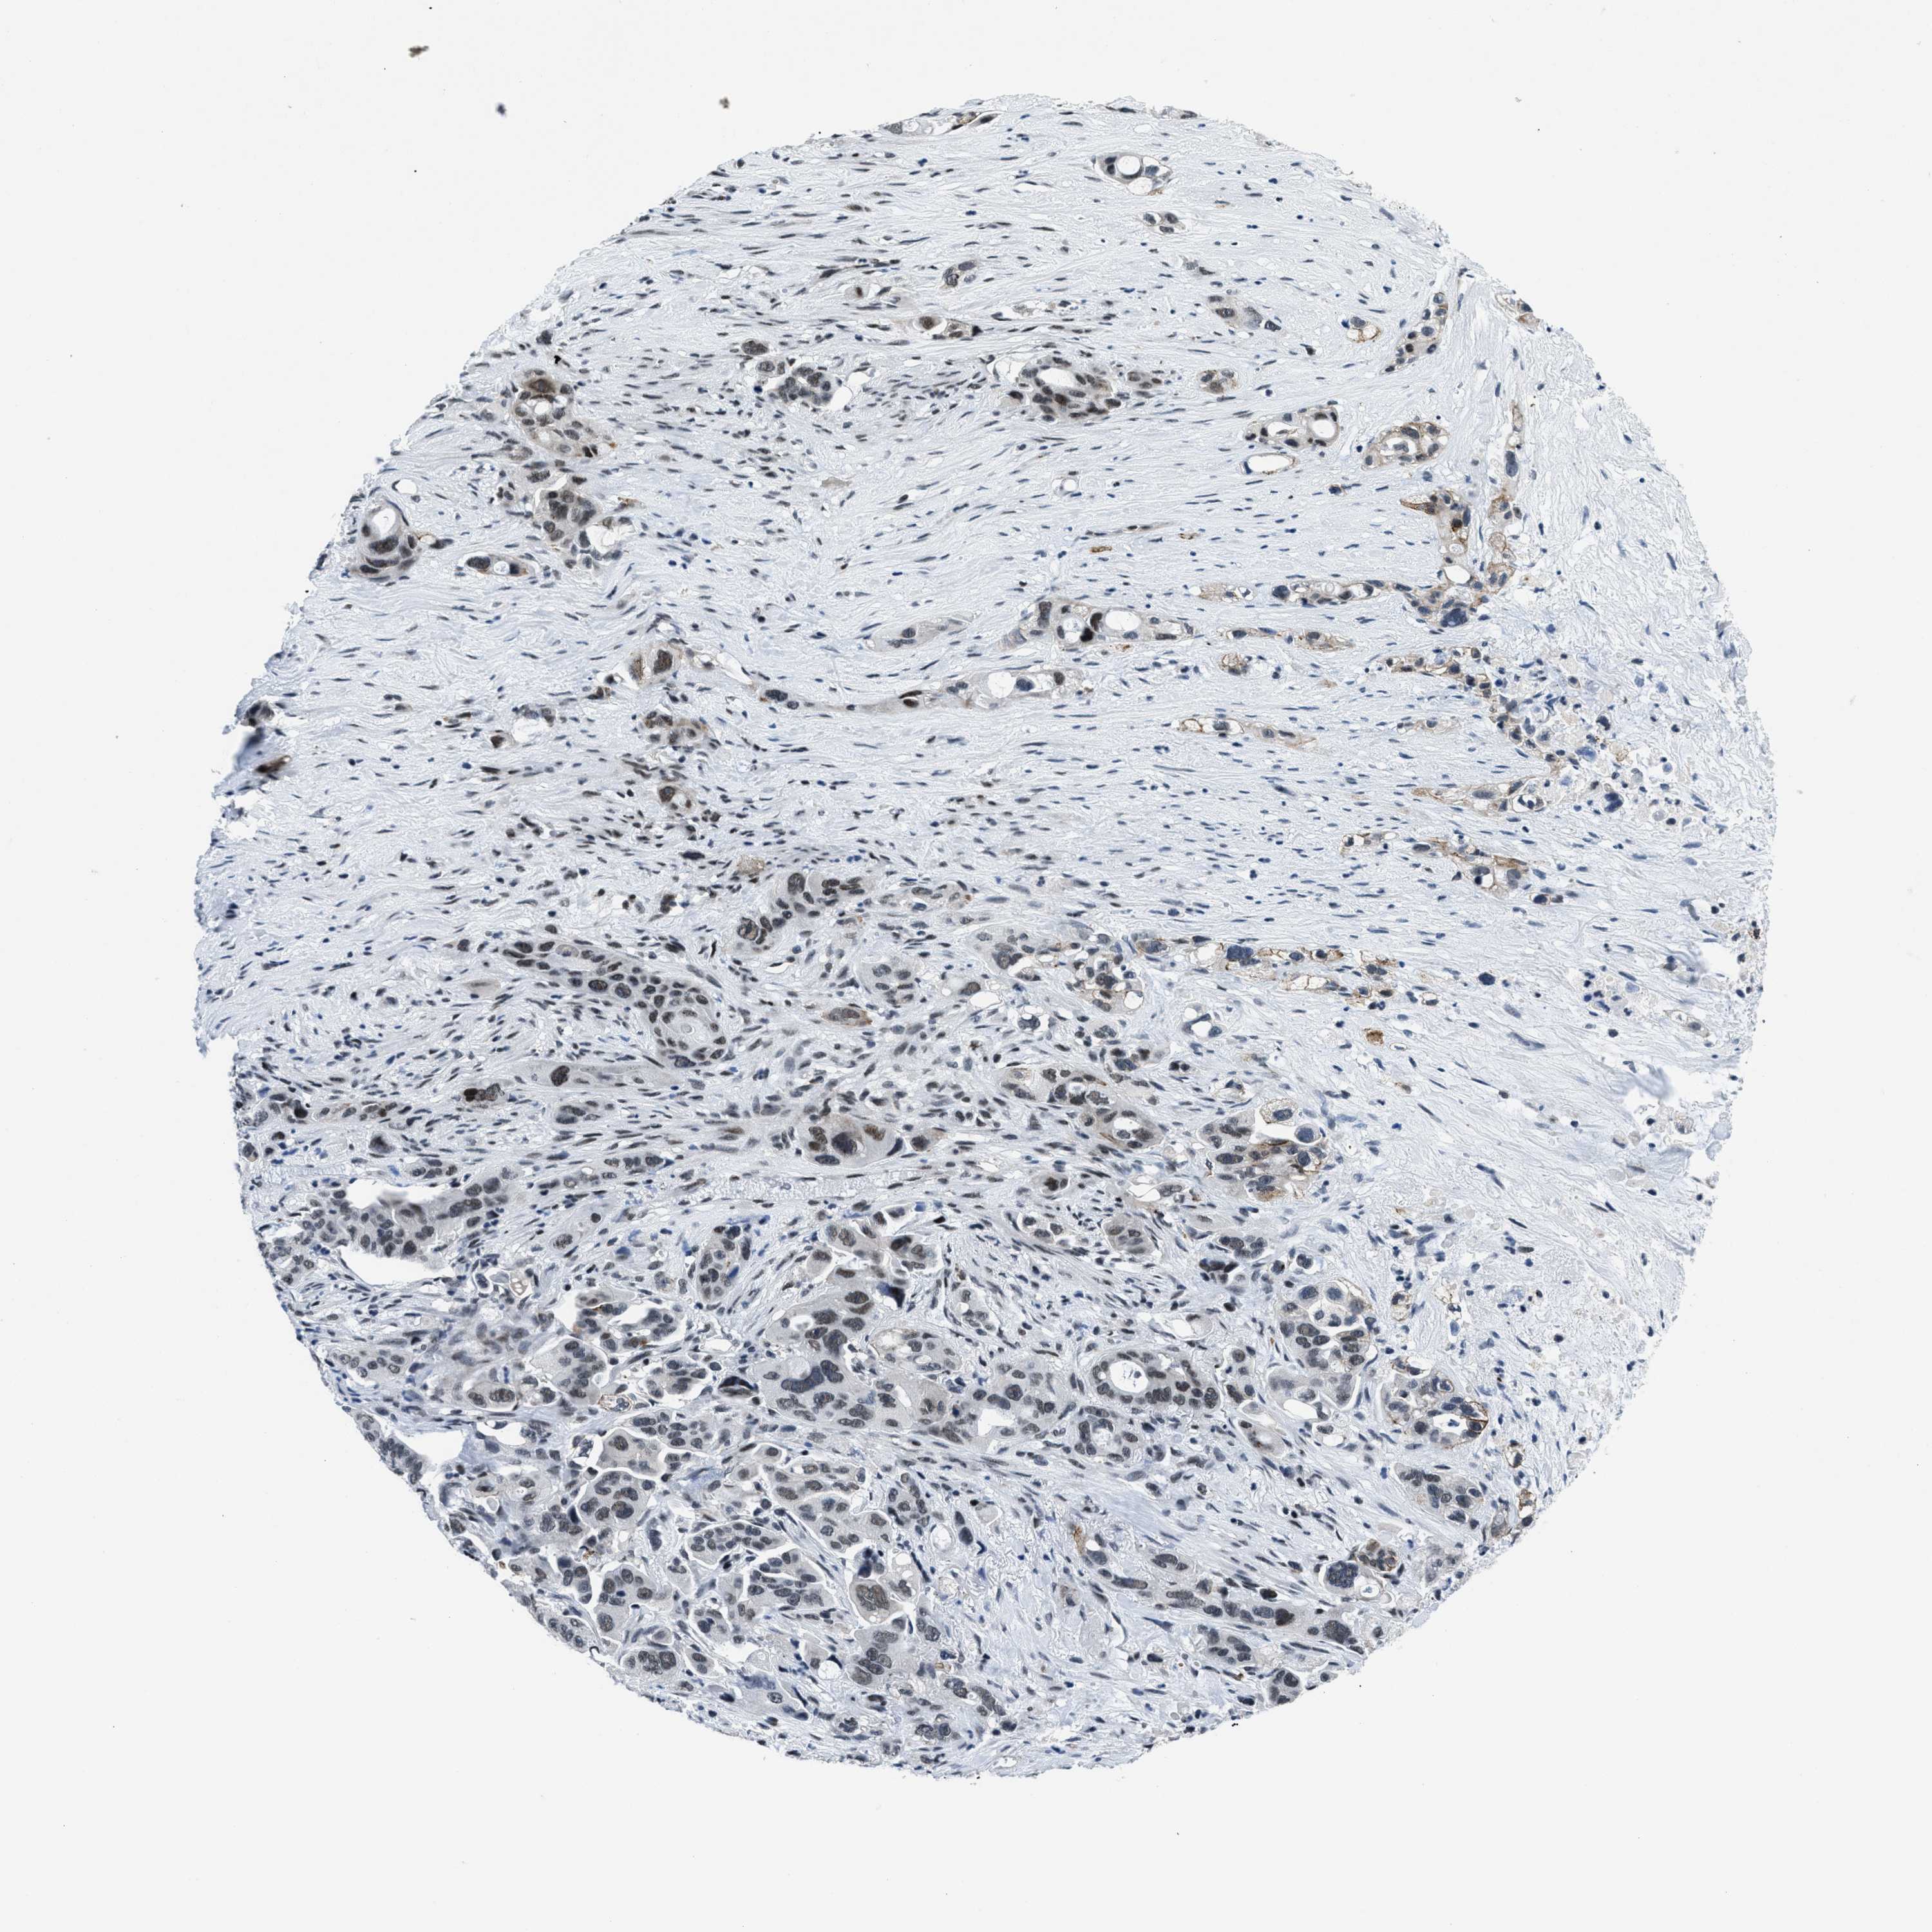

PANCREATIC CANCER - Protein expressioni

A mouse-over function shows sample information and annotation data. Click on an image to view it in a full screen mode. Samples can be filtered based on level of antibody staining by selecting one or several of the following categories: high, medium, low and not detected. The assay and annotation is described here.

Note that samples used for immunohistochemistry by the Human Protein Atlas do not correspond to samples in the TCGA dataset.

Antibody stainingi

Antibody staining in the annotated cell types in the current human tissue is reported as not detected, low, medium, or high, based on conventional immunohistochemistry profiling in selected tissues. This score is based on the combination of the staining intensity and fraction of stained cells.

Each image is clickable and will lead to virtual microscopy that enables deeper exploration of all samples and also displays staining intensity scores, fraction scores and subcellular localization as well as patient and tissue information for each sample.

Antibody HPA018248

Antibody HPA019127

Antibody CAB009196

Staining

High

Medium

Low

Not detected

Intensity

Strong

Moderate

Weak

Negative

Quantity

>75%

75%-25%

<25%

None

Location

Nuclear

Cytoplasmic/membranous

Cytoplasmic/membranous,nuclear

Adenocarcinoma, NOS

Adenocarcinoma, metastatic, NOS